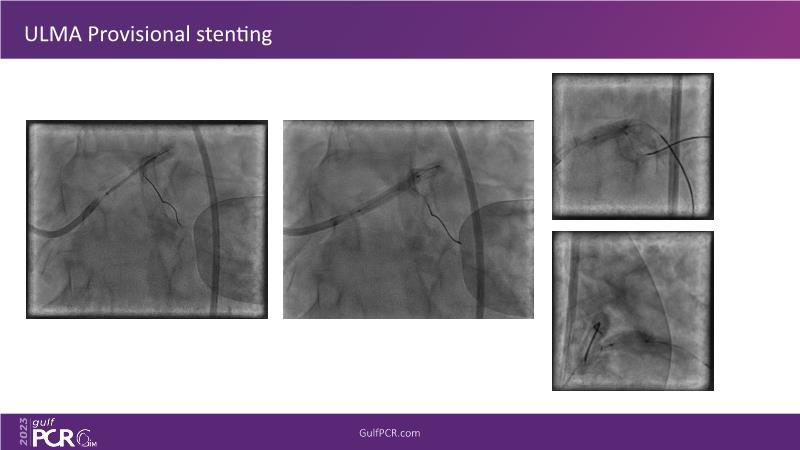

Watch this session to learn all about the intravascular lithotripsy (IVL) mechanism for treating calcified lesions. Discover practical advice and techniques for implementing IVL in challenging calcified lesions and the safe utilization of IVL in left main bifurcations.

- To learn how to safely utilise intravascular lithotripsy in left main bifurcations